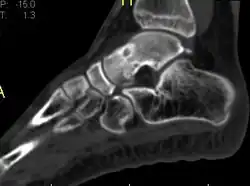

Radiographs in osteoid osteoma typically show a round lucency, containing a dense sclerotic central nidus (the characteristic lesion in this kind of tumor) surrounded by sclerotic bone. The nidus is seldom larger than 1.5 cm.

The lesion can in most cases be detected on CT scan, bone scans and angiograms. Plain radiographs are not always diagnostic. MRI adds little to the CT findings which are useful for localisation. Radionuclide scanning shows intense uptake which is useful for localisation at surgery using a hand held detector, and for confirmation that the entire lesion has been removed.[8][9]